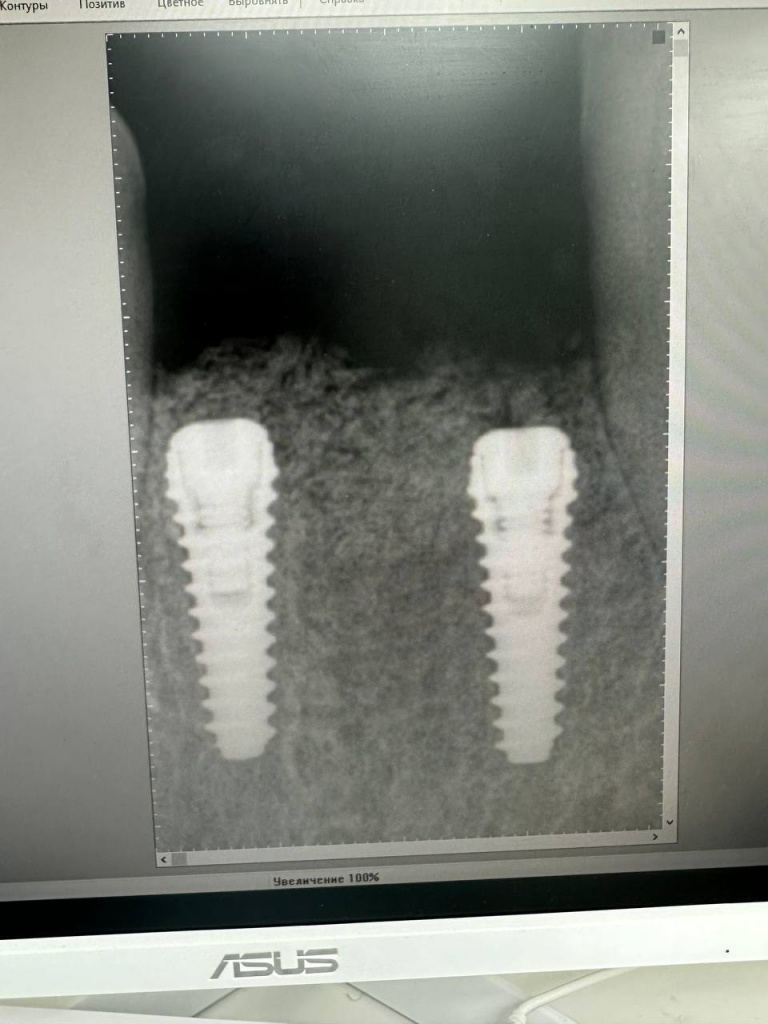

Уже много лет использую в своей практике имплантаты IMPRO. В этот раз мне предоставили линейку IMPRO Respect нового дизайна с широкими лепестками резьбы по отношению к телу имплантата. За счет чего получилось установить имплантаты в переднем отделе в узком гребне и с плохим костным предложением пациента. Ни разу не сталкивалась с осложнениями или проблем с имплантатми IMPRO Implantem. В этот раз не было исключением, была проведена операция через навигационный шаблон, имплантаты стабилизировались с хорошим торком. Хирургический набор и протоколы достаточно просты и удобны. Будем ждать ортопедической части, спустя месяц имплантаты стоят хорошо!

Пациент — мужчина 54 года.